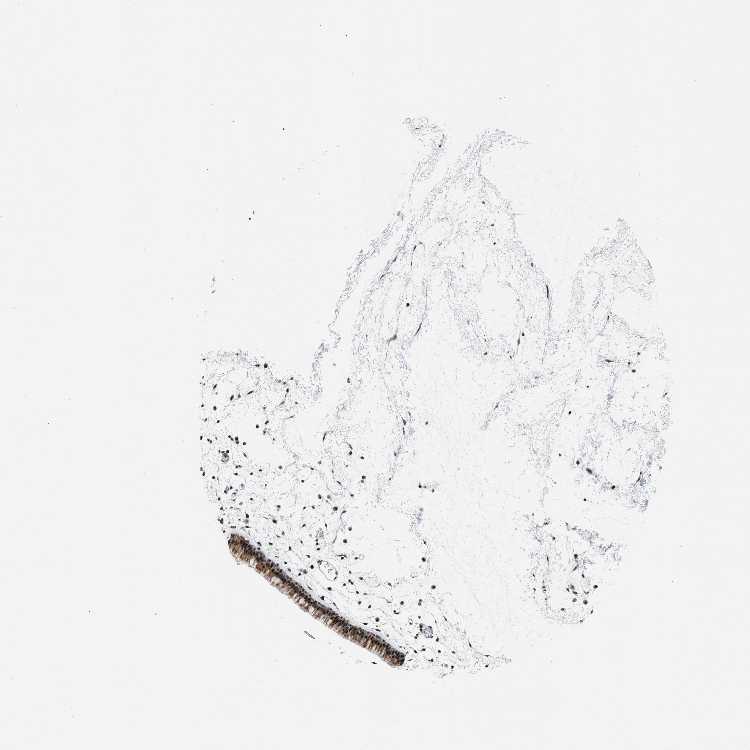

TISSUE PRIMARY DATA NASOPHARYNX Show tissue menu

NASOPHARYNX - Antibody stainingi

Antibody staining in the annotated cell types in the current human tissue is reported as not detected, low, medium, or high, based on conventional immunohistochemistry profiling in selected tissues. This score is based on the combination of the staining intensity and fraction of stained cells.

Each image is clickable and will lead to virtual microscopy that enables deeper exploration of all samples and also displays staining intensity scores, fraction scores and subcellular localization as well as patient and tissue information for each sample.

Antibody HPA021787

Respiratory epithelial cells Medium